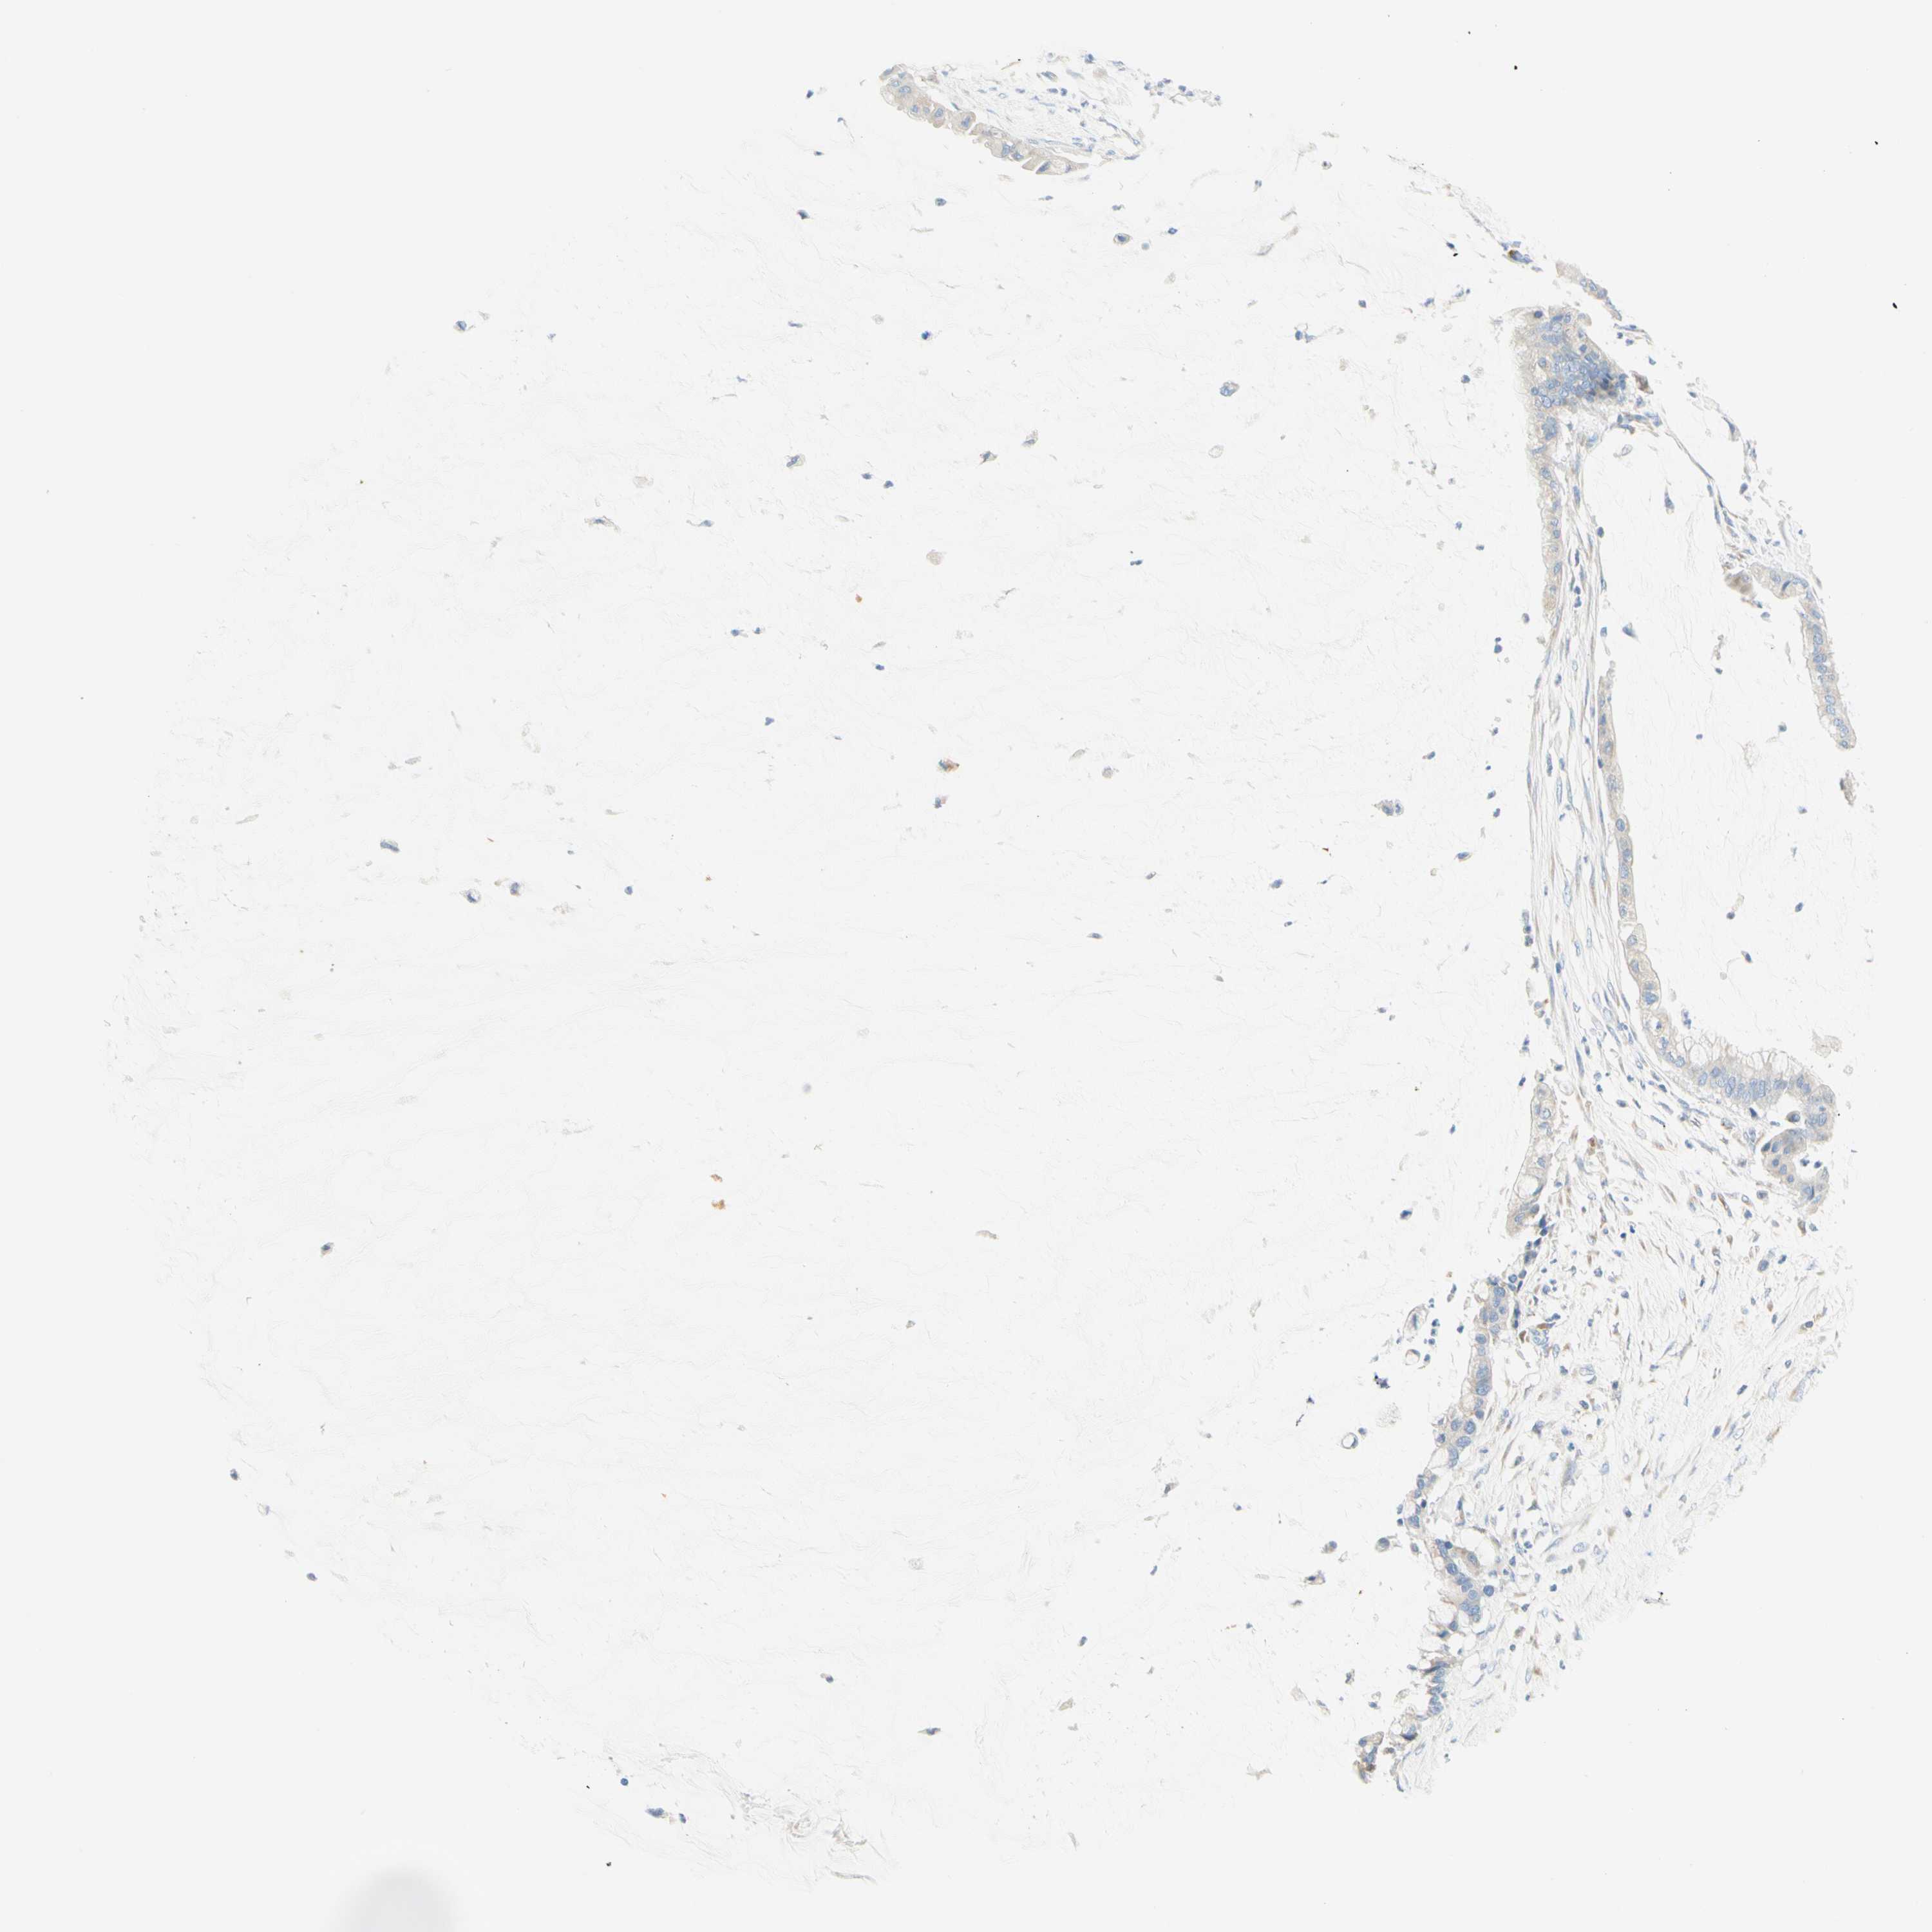

PANCREATIC CANCER - Protein expressioni

A mouse-over function shows sample information and annotation data. Click on an image to view it in a full screen mode. Samples can be filtered based on level of antibody staining by selecting one or several of the following categories: high, medium, low and not detected. The assay and annotation is described here.

Note that samples used for immunohistochemistry by the Human Protein Atlas do not correspond to samples in the TCGA dataset.

Antibody stainingi

Antibody staining in the annotated cell types in the current human tissue is reported as not detected, low, medium, or high, based on conventional immunohistochemistry profiling in selected tissues. This score is based on the combination of the staining intensity and fraction of stained cells.

Each image is clickable and will lead to virtual microscopy that enables deeper exploration of all samples and also displays staining intensity scores, fraction scores and subcellular localization as well as patient and tissue information for each sample.

Antibody HPA011157

Antibody CAB002223

Antibody CAB012978

Antibody CAB079960

Staining

High

Medium

Low

Not detected

Intensity

Strong

Moderate

Weak

Negative

Quantity

>75%

75%-25%

<25%

None

Location

Nuclear

Cytoplasmic/membranous

Cytoplasmic/membranous,nuclear

Adenocarcinoma, NOS

Adenocarcinoma, metastatic, NOS